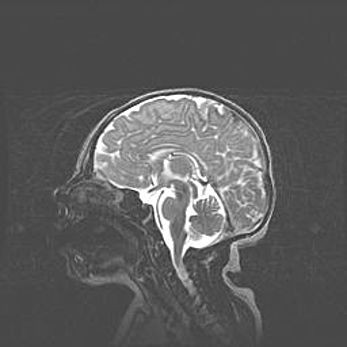

Аномалия Денди-Уокера. Признаки гипоплазии мозолистого тела.

Возраст: 5 месяцев 3 дня

Вес: 5550 г

Пол: мужской

Окружность головы: 39 см

Срок гестации: 40 недель

Аномалия Денди-Уокера – это порок развития головного мозга, для которого характерна триада симптомов: гипотрофия или аплазия червя мозжечка и/или полушарий мозжечка, расширение четвёртого желудочка с формированием ликворной кисты задней черепной ямки, гипертензионная гидроцефалия различной степени.

Гипоплазия мозолистого тела относится к дефектам внутриутробного этапа развития мозговой ткани, возникающим в процессе закладки структур головного мозга, что происходит на начальных этапах развития эмбриона.